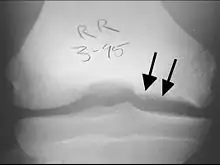

X-rays show lucency of the ossification on the anterior aspect of the knee in juvenile patients. In older people, the lesion typically appears as an area of osteosclerotic bone with a radiolucent line between the osteochondral defect and the epiphysis. The visibility of the lesion depends on its location and on the amount of knee flexion used. Harding described the lateral X-ray as a method to identify the site of an OCD lesion.[36]

CT scan and projectional radiography of a case of osteochondritis dissecans of parts of the superio-medial talus. -